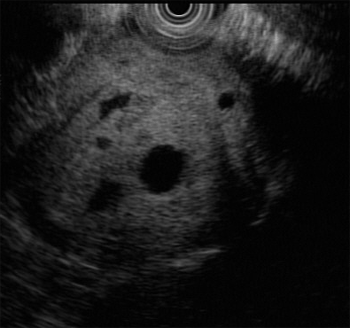

내시경초음파 유도하 세침흡인(EUS-FNA)을 시행하였다. 흡인된 낭액은 혈성(bloody)이었고 (Fig. 3), 낭액 분석 (cystic fluid analysis) 결과는 CEA 0.5 ng/mL, CA 19-9 128.2 μ/mL, amylase/lipase 42/26 U/L였다.

Figure 3. EUS guided cystic fluid aspiration

췌장 낭성 병변의 감별진단에 EUS-FNA를 통한 낭액분석이 도움된다는 보고들이 있다. 점액성 낭종 (mucinous cystic neoplasm)과 비점액성 낭종 (non-mucinous cystic neoplasm)의 감별에 가장 유용한 검사는 낭액에서 CEA를 검사하는 것이다. CEA의 cut-off value는 연구자마다 차이가 있으나, Brugge 등1의 다기관 연구에서는 192 ng/mL (민감도; 73~85%, 특이도; 83~84%)였다. 일반적으로 수치가 높을수록 점액성 낭종의 가능성이 크다. 낭액의 점도 및 색깔도 감별진단에 도움이 된다. 본 환자의 경우 CEA 값이 0.5 ng/mL 로 매우 낮고, 낭액이 혈성이었고, 점도도 낮아 낭액 분석만으로도 SPT(solid pseudopapillary tumor)를 의심할 수 있었다.